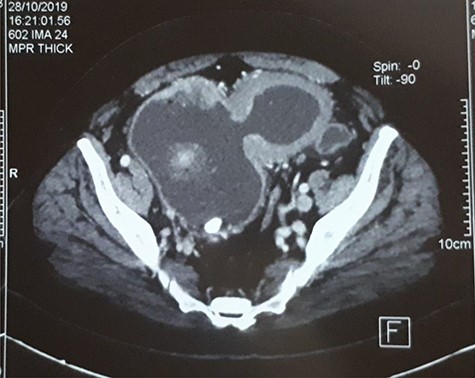

A 63-year-old man with a history of transurethral resection of prostate and a ballistic lithotripsy of bladder stone 15 years ago, presented with low urinary tract symptoms and hematuria. Cystoscopy showed multiple bladder stones and a bulky tumor mainly intradiverticular (Fig. 1). Partial resection of the tumor was done and pathology concluded on a squamous cell invasive bladder carcinoma. Since staging showed no metastatic lesion, a cystoprostatectomy was decided. Its execution was delayed because of a pulmonary embolism treated with curative anticoagulation and a severe paraneoplastic hypercalcemia treated with Zoledronic acid and veinous hydration on hospitalization. At Day 10 from admission and Day 60 after endoscopic resection of the tumor, the patient complained of abdominal pain, with diffuse tenderness and fever. Biology shows biologic inflammatory syndrome and kidney failure. Peritonitis was suspected and CT-scan showed a perforated bladder diverticulum with intraperitoneal effusion (Fig. 2). An emergency surgical investigation was executed, objecting a peritoneal cavity filled with nauseating hematic urine derived from a 2 cm disruption at the level of a posterolateral bladder diverticulum (Fig. 3). Radical cystectomy was performed. The patient was in severe septic shock requiring catecholamines and the procedure had to be shortened. No pelvic lymphadenectomy was done and bilateral ureterostomy was chosen as urinary diversion. The intervention lasted 2 h and there was no significant blood loss.

CT-scan of the bladder 2 months before the rupture showing bladder tumor in the dome and in intradiverticular and a bladder stone.